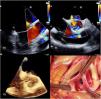

A 22-year-old male was admitted to the emergency room due to a left hemithorax injury from a screwdriver (Figure 1A). The patient was hemodynamically stable, with a slightly altered mental status. Chest computed tomography was performed and revealed moderate pericardial effusion, leading to an evaluation by the cardiology emergency team. The transthoracic echocardiogram revealed severe aortic valve regurgitation, raising suspicion of aortic root injury, as well as fistulous communications between heart chambers (Figure 1B–D). These findings led to emergent surgery.

Chest wall lesion (A) and transthoracic echocardiographic images showing a circumferential and large pericardial effusion (B), as well as turbulent flow in aortic root and a severe aortic valve regurgitation (C); fistulous communications between both the right ventricle and left atrium to the aortic root were suspected in the parasternal short axis view (D).